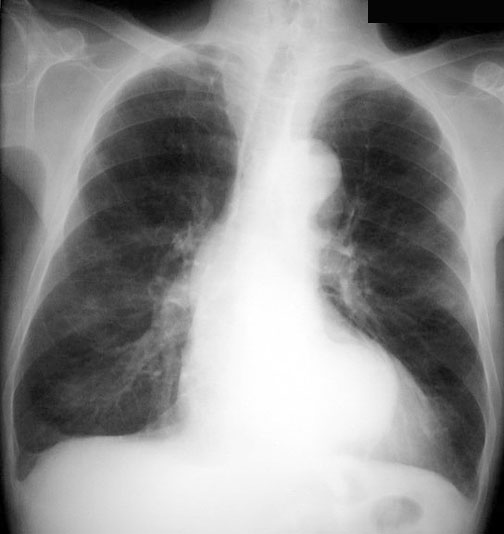

Inhomogeneous Cardiac Density / Double Density

The heart should be of uniform density, except over the vertebra and descending aorta. Left atrial enlargement can be recognized by the circular double density. Any time you see increased density in one portion compared to the rest of the heart, consider an abnormal density either in front of or behind the heart. Consider the following when you encounter inhomogeneous cardiac density:

This is an example of an aorta aneurysm.